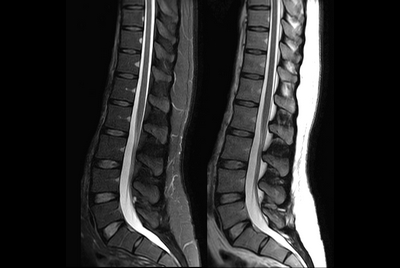

Whole Spine with scoliosis ( 2 stations )